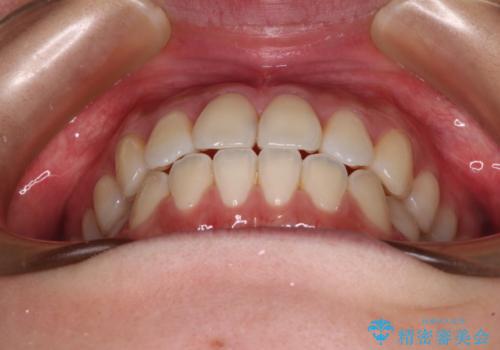

- 前歯のクロスバイトが気になり、インビザラインによる矯正治療を希望して来院された患者様です。

上顎側切歯(上の真ん中から2番目の歯)が舌側転位している場合、インビザラインでは仕上げきれないことが多く、更には無理して動かそうとすると歯髄壊死を起こすリスクが高いと言われています。

インビザラインで歯列を移動する前に、上顎前歯をワイヤー矯正で整え、その後上下歯列をインビザラインにて矯正治療を行うこととしました。

舌側転位している側切歯特有の、切縁の位置が不揃いであったり、根元が内側に引っ込んだ状態であったりという、インビザライン独特の仕上がりになることなく、きれいに整った歯列とすることができました。